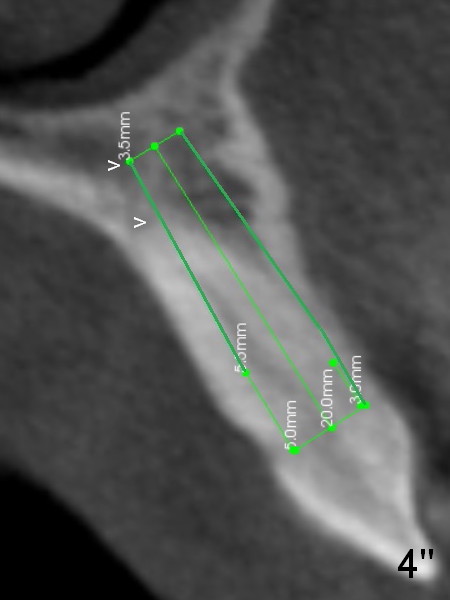

Lengthwise, a longer osteotomy is needed (Fig.4): 20 mm at the gingival level, 17 mm at the bone level. Distal to the 5 mm tap is a gap (*). Initially a shorter osteotomy (by 3 mm) is made: there is minimal engagement with the labial bone (Fig.4' between arrowheads (CT coronal section from not the same patient)). The osteotomy is extended (Fig.4''). This is the second problem to be solved.